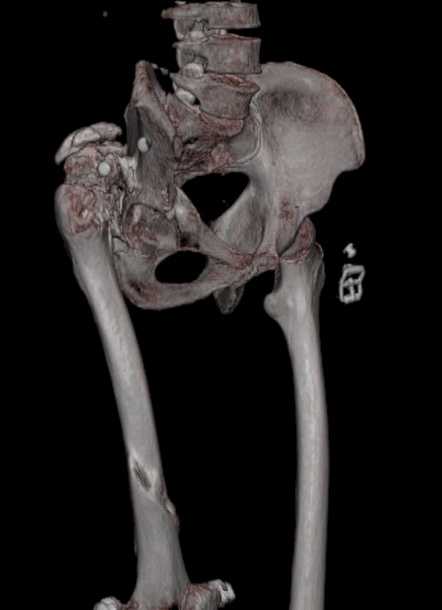

Уважаемые коллеги. Пациент 30 лет 3 года назад в результате травмы получил травматический дефект нижних конечностей до в/3 голеней, был пропущен вывих бедра.

В настоящее время очень неплохо ходит на протезах, движения в неоартрозе близки по объему к здоровой стороне. Основная жалоба - выраженная боль при ходьбе. планируем двухэтапное эндопротезирование - задним доступом мобилизовать проксимальный отдел бедра, резецировать шейку, аппаратом низвести бедро(головку оставить там где она есть, так как больших дефектов не видно(может пригодится в последующем?)). Вторым этапом бесцементное эндопротезирование. Насколько такой вариант реалистичен? Доступ для второго этапа? Может быть другие варианты?С уважением, Максим

На последнем срезе КТ задний край практически отсутсвует по сравнения со здоровой стороной. Разумеется, что это плоскостное изображение, но головка вывихнулась не только в плоскостную щель захваченную на КТ. Если вы считаете, что удастся установить туда чашку даже низкопрофильную, остается пожелать вам успехов. Но перед этим можно смоделировать установку чашки на скиаграммах КТ.

За пожелание успехов - спасибо, думаю это пригодится, не очень понял про плоскостную щель, специально предоставил срезы на уровне свода - он цел, дефект заднего края ниже, за счет заглубления он будет еще меньше, по данным 3d - должно получиться.

Низводить надо обязательно, лучше в аппарате и лучше без остеотомии.

Если в аппарате низводиться не будет, то из небольшого доступа, лучше под контролем С-дуги выполнить остеотомию шейки. Без предварительного

низведения максимально возможная коррекция длины - 2,5-3 см.

Решение по ВВ придется принимать по месту.... Сумеете "подрыться" и получить хорошее покрытие чашки (+2 винта об-но) - хорошо, если нет -

костная аутопластика из головки.